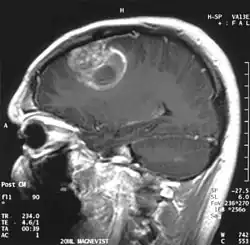

Мультиформная глиобласто́ма (англ. Glioblastoma multiforme, GBM) — наиболее частая и наиболее агрессивная форма опухоли мозга, которая составляет до 52 % первичных опухолей мозга и до 20 % всех внутричерепных опухолей. Несмотря на то, что глиобластома является наиболее частой первичной опухолью мозга, на 100 000 жителей Европы и Северной Америки регистрируется всего 2—3 случая заболевания[1]. Термин «глиобластома» подразумевает два варианта этой болезни: гигантоклеточная глиобластома и глиосаркома.